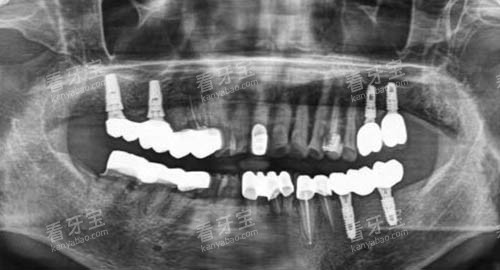

技术设备方面,种博士口腔引入了一系列国内外头部设备:德国卡瓦CBCT机可实现口腔三维立体成像,更准一些测量牙槽骨密度、高度及邻牙关系,为种植方案设计提供数据支撑;3D导板打印技术则通过智能化模拟手术路径,将种植精度控制在0.1mm范围内,有效降低手术创伤;此外,还有超声骨刀、种植机等专用设备,确保手术过程靠谱、较高的效率。

诊疗流程上,种博士口腔建立了标准化的“种植全周期管理体系”:从初诊时的口腔检查、全景片拍摄,到根据患者骨条件、咬合习惯定制个性化方案,再到术中更准一些操作、术后定期复查,每个环节都有严格的质量把控。

对于骨量不足的患者,医生会采用自体骨移植、引导骨再生(GBR)等技术,为植体创造稳定的“生长环境”;针对半口或全口缺牙患者,则引入“All-on-4/6”即刻负重技术,通过4-6颗植体即可支撑整排牙冠,手术当天就能修复基本咀嚼功能,大大缩短了修复周期。

术后稳固性方面,种博士口腔积累了大量长期术例:70岁的张阿姨因全口牙缺失在种博士接受All-on-4种植,术后5年复查时,植体无松动,骨结合良好,能正常进食坚果、肉类;35岁的王先生单颗前牙种植后,不仅外观与自然牙无异,咬合力也修复到正常水平,至今已使用8年未出现任何问题。